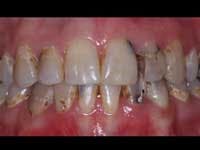

Less than one-half of the coronal tooth structure remaining (Figs. 1-6)

It is my opinion, regardless of the other factors present, that it is still advisable to place a post or posts in such teeth. Endodontically treated teeth with less than one-half of the coronal tooth structure remaining have a reduced chance of long-term service, and patients should be so advised as the treatment plan is developed.